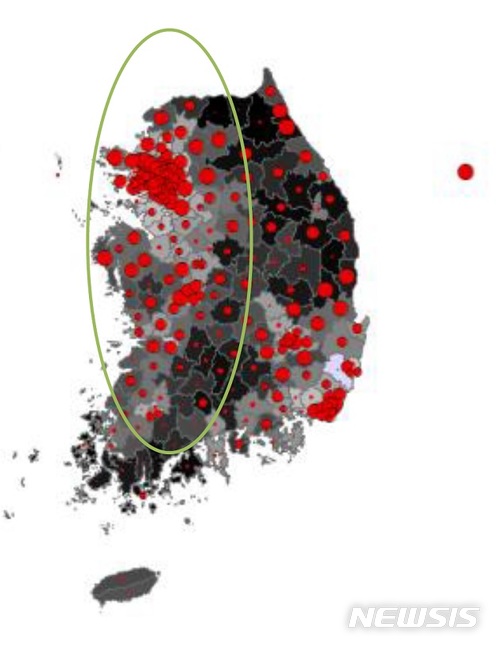

【세종=뉴시스】이인준 기자 = 빛공해가 심각한 지역에서 사는 여성의 유방암이 발생할 확률이 그렇지 않은 지역보다 24.4% 높다는 분석 결과가 제기됐다.

이 교수팀도 이번 심포지엄에서 국외에서 '빛 공해가 심각한 지역에 사는 여성은 다른 지역 여성에 비해 유방안이 발생할 확률이 73% 더 높다'는 연구결과를 바탕으로 국내 연구를 진행했다.

연구팀은 전국 각 지역의 빛공해 수준을 비교 가능한 수준으로 평균화하고, 지역과 유방암 환자수의 상관 관계를 분석했다. 그 결과 빛공해 오염이 심각한 지역은 최대 유방암 유병률이 24.4% 증가하는 것으로 집계됐다. 시골 지역의 경우에도 최대 11.4 % 증가하는 것으로 조사됐다.